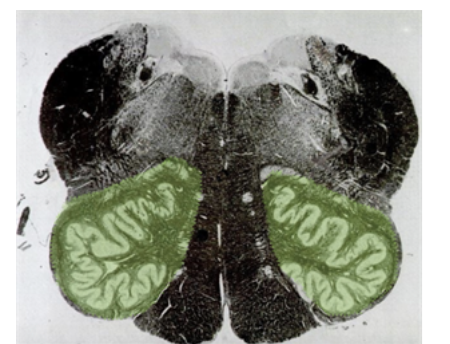

What brainstem level is this?

Whats the shape of the rostral pons kind of resemble?